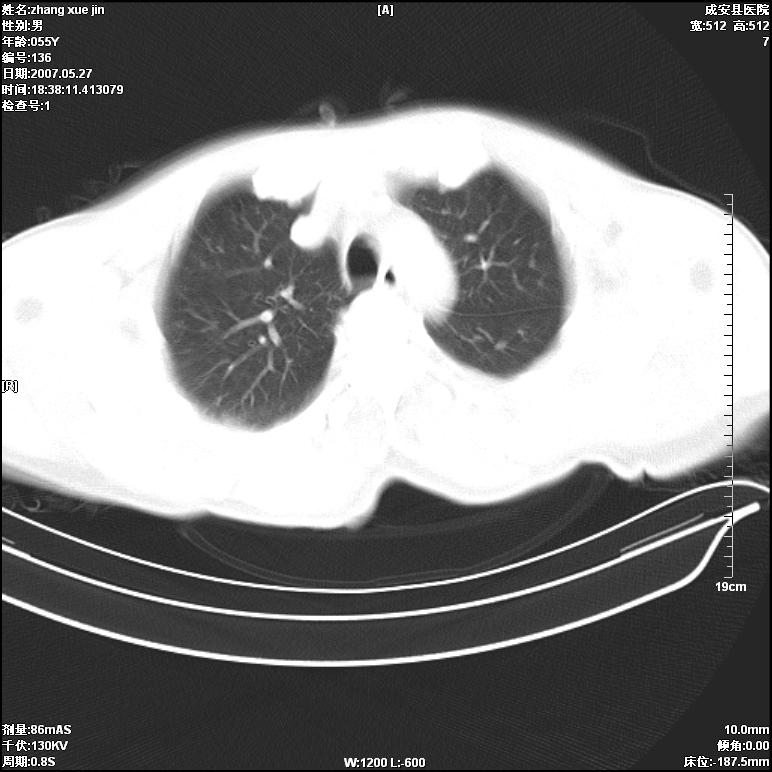

病人 男 53岁 从高处摔伤 行胸部ct检查,纵隔窗没事未上传,肺窗示,右侧胸膜下见条状稍高密度影,是胸膜下线还是右下肺轻度挫伤?意见不一,请分析。

右肺下叶胸膜下弧形窄带状模糊影,结合病史,考虑肺挫伤。

建议一周后复查,肺挫伤一般3~10天完全吸收。

左肺亦有,建议深吸气后扫描,你们是技术员扫描吧。

体位不正,左侧纵隔旁胸膜下亦见条带状略高密度影,考虑为坠积效应所致。

气管内见一小液平面,